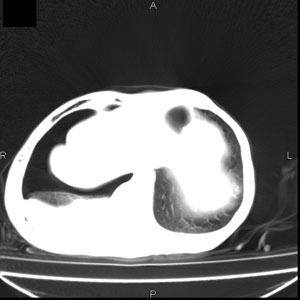

患者男,77岁,于3日前从树上摔下,头部查ct示蛛血,硬膜下出血,上腹部ct未见明显异常,右侧胸腔积液,左侧如常。肺部拍片示右侧肋骨多发骨折住院后今日来查肺部ct,我看到的是1。右侧胸腔血气胸并右肺上叶,中叶压缩性肺不张,2。右肺下叶肺挫伤并多发肋骨骨折,肌内及皮下积气3。左侧少量胸腔积液,我想请教的是3天前左侧胸腔里没有积液今天怎么出现了呢,是什么原因呢?请讨论。

回复楼主   左侧液气胸,液体来源1、肯定有血液成分,多少不一定。2、胸膜腔渗液,由于肺压缩、活动度下降,肯定胸膜吸收有问题,导致积液增多。

支持楼主诊断。液体来源:1、血液成分,外伤所致。2、胸膜腔渗液—由于肺压缩、活动度下降,肯定胸膜吸收有问题,导致积液增多。

右侧液气胸,胸膜创伤、肺组织挫伤,渗出属正常反应。

右侧多发肋骨骨折,同侧液气胸

支持左侧液气胸

左侧液气胸,液体来源1、肯定有血液成分,多少不一定。2、胸膜腔渗液,由于肺压缩、活动度下降,肯定胸膜吸收有问题,导致积液增多

张力性气胸